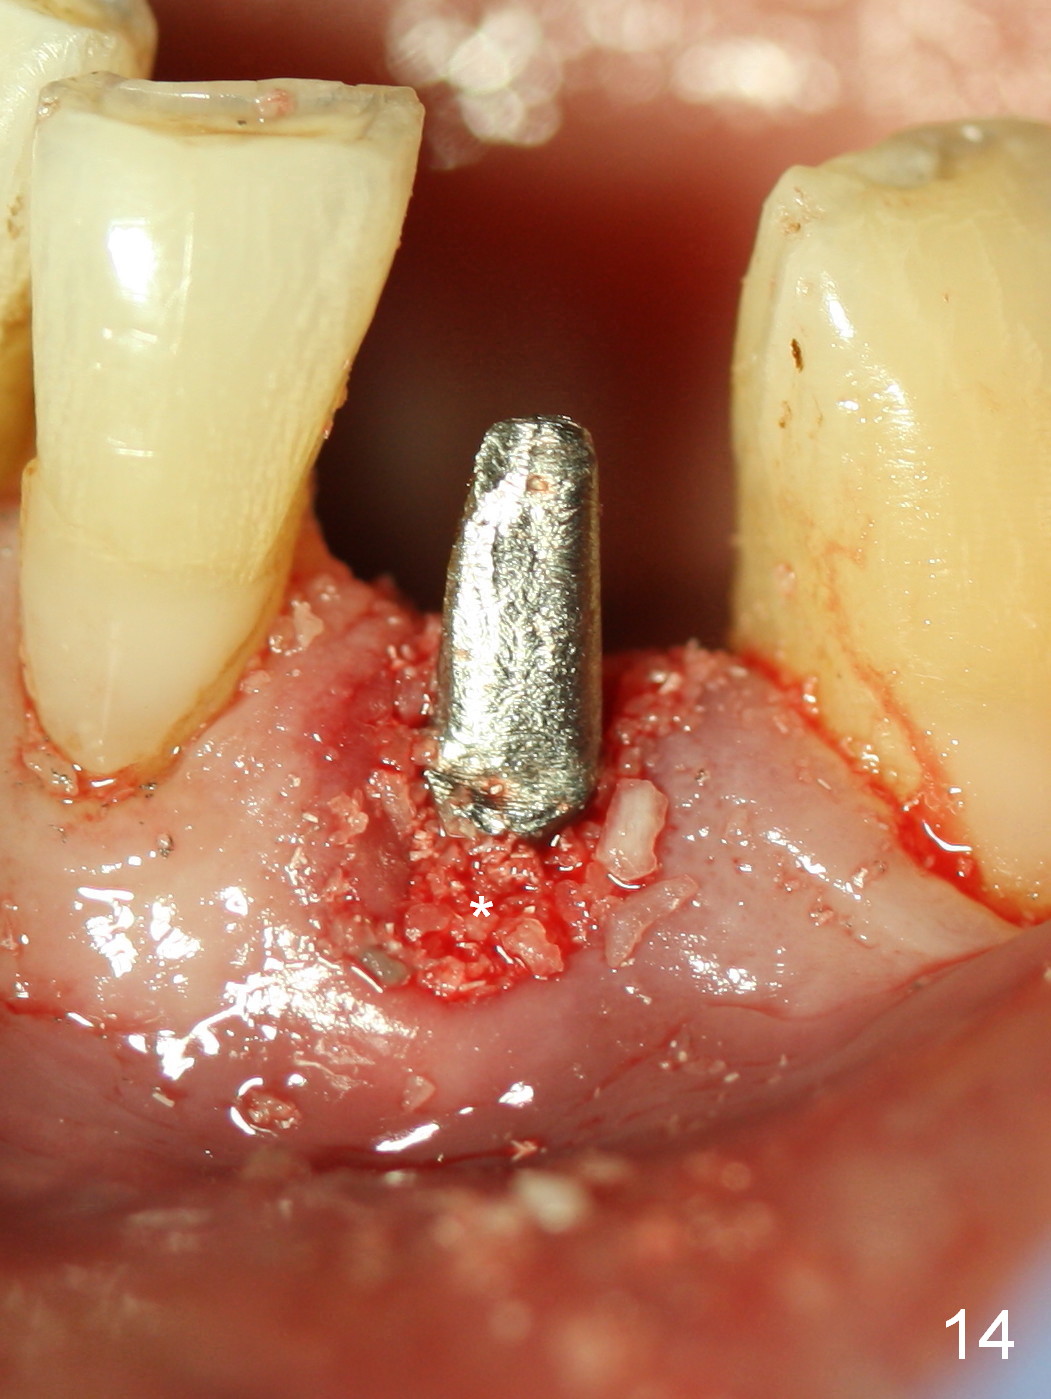

A 74-year-old man has several missing teeth (Fig.1).  His 1st goal is to replace the lower left lateral incisor (Fig.2).  The residual root has an apical lesion (Fig.3 *).  To describe intraop findings, a CT image of a different patient is used (Fig.4 coronal section; B: buccal; L: lingual).  After extraction, the buccal plate is found to be thin and low (Fig.5 arrowheads).  A 1.5 mm pilot drill (Fig.6 red line) is used to initiate osteotomy in the lingual plate of the socket.  Once the drill penetrates the lingual plate, the trajectory changes and the depth is 17 mm from the gingival margin (Fig.7).  A PA is taken (Fig.8); it appears that the osteotomy can be extended more apically.  When the pilot drill extends to 20 mm, there is sudden empty feeling.  The lingual plate has perforated (Fig.9).  A new osteotomy is established buccally (Fig.10 pink).  To avoid buccal plate perforation, especially in the buccal undercut area (>), the coronal end of the drill has to be tilted buccally (<--).  An angled abutment (3x20 mm, 15°) is placed (Fig.11,12).  The abutment is modified (Fig.13,14) to accommodate an immediate provisional (Fig.15,16 P).  Perio dressing is to be applied to prevent the bone graft from getting dislodged buccally (Fig.15).  The dressing is in place 7 days postop (Fig.17).